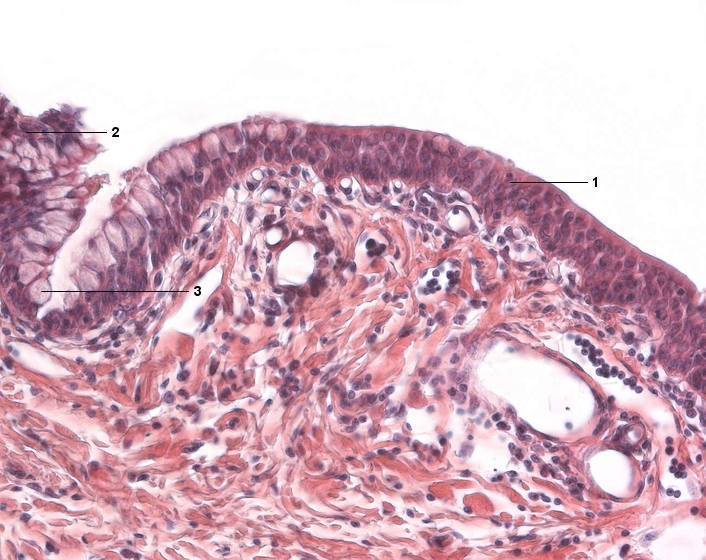

1 mehrschichtig unverhorntes Epithel

2 Epithel der Conjunctiva

3 Becherzelle